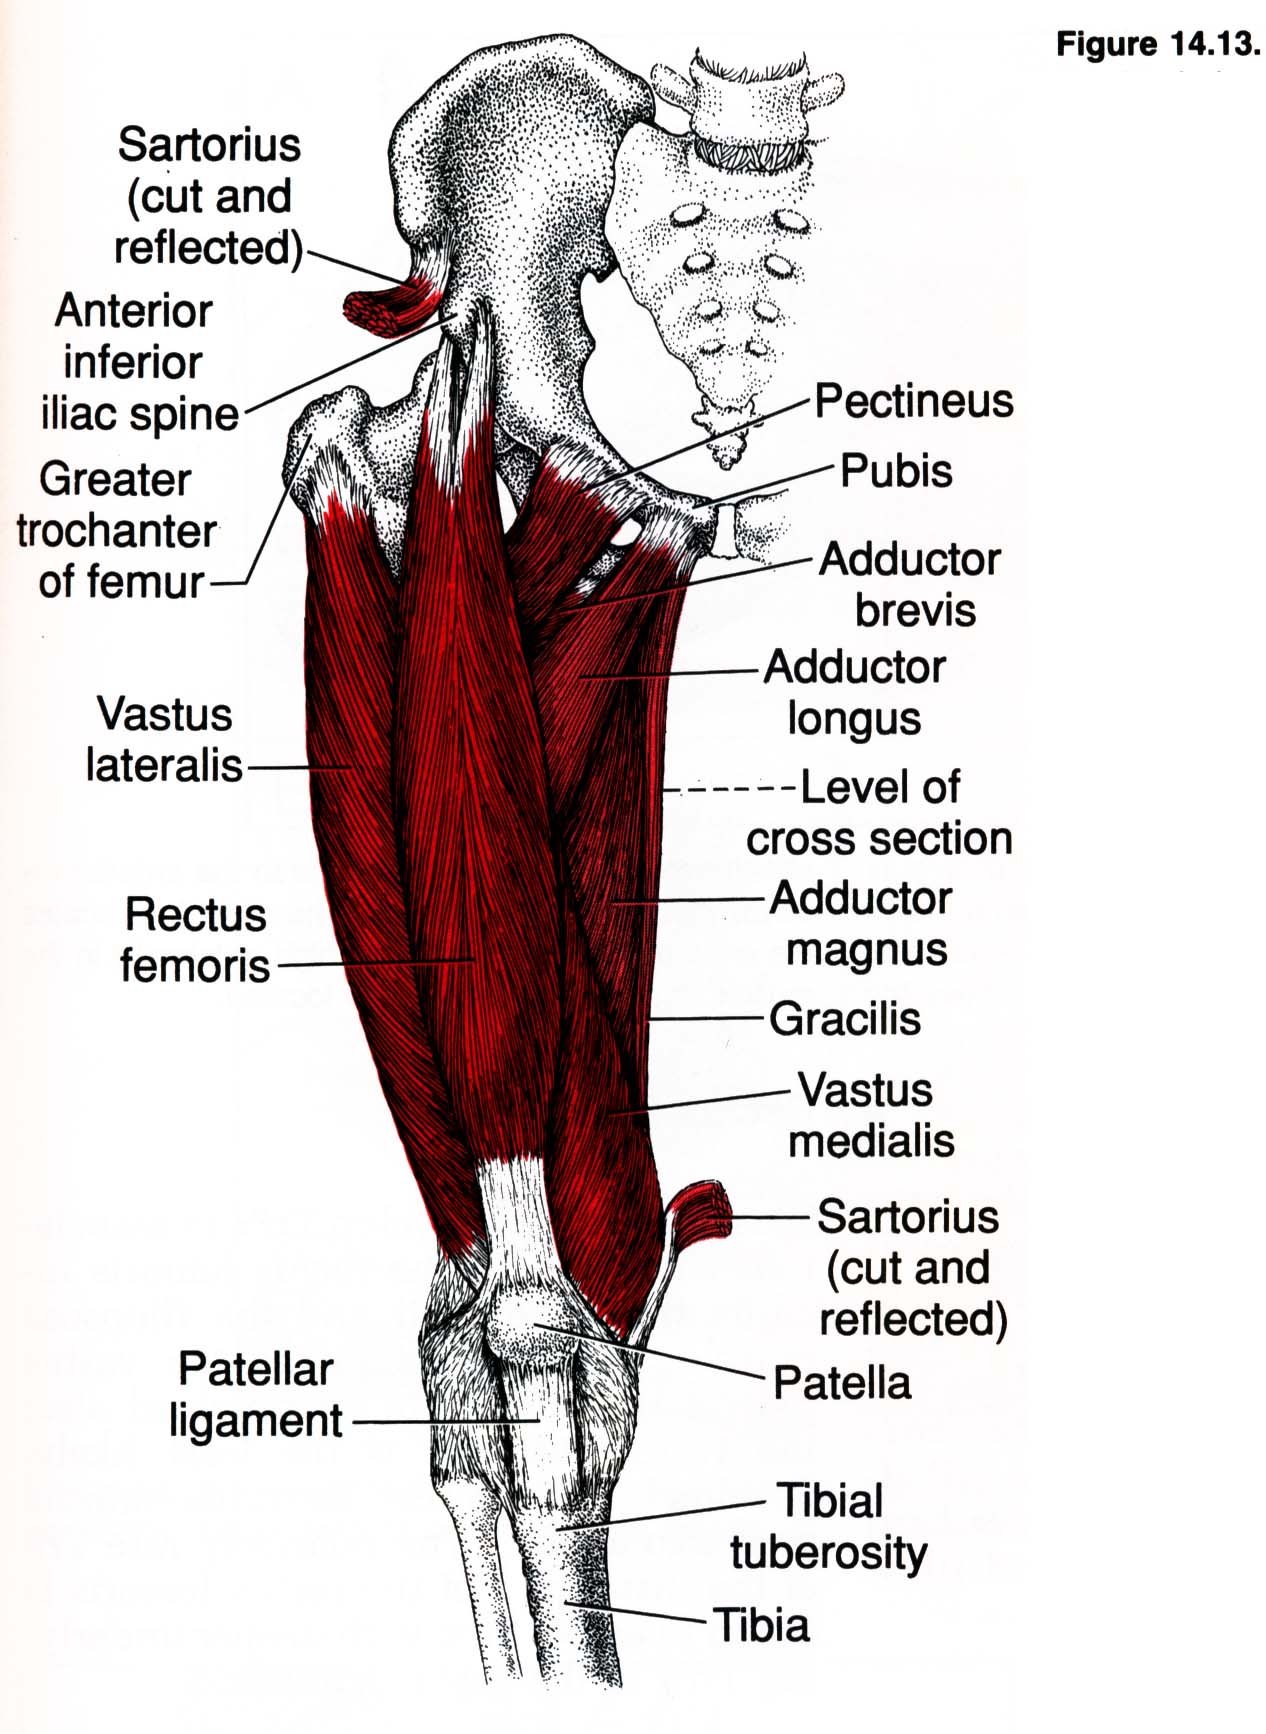

Анатомия и Функции Мышцы Adductor Magnus